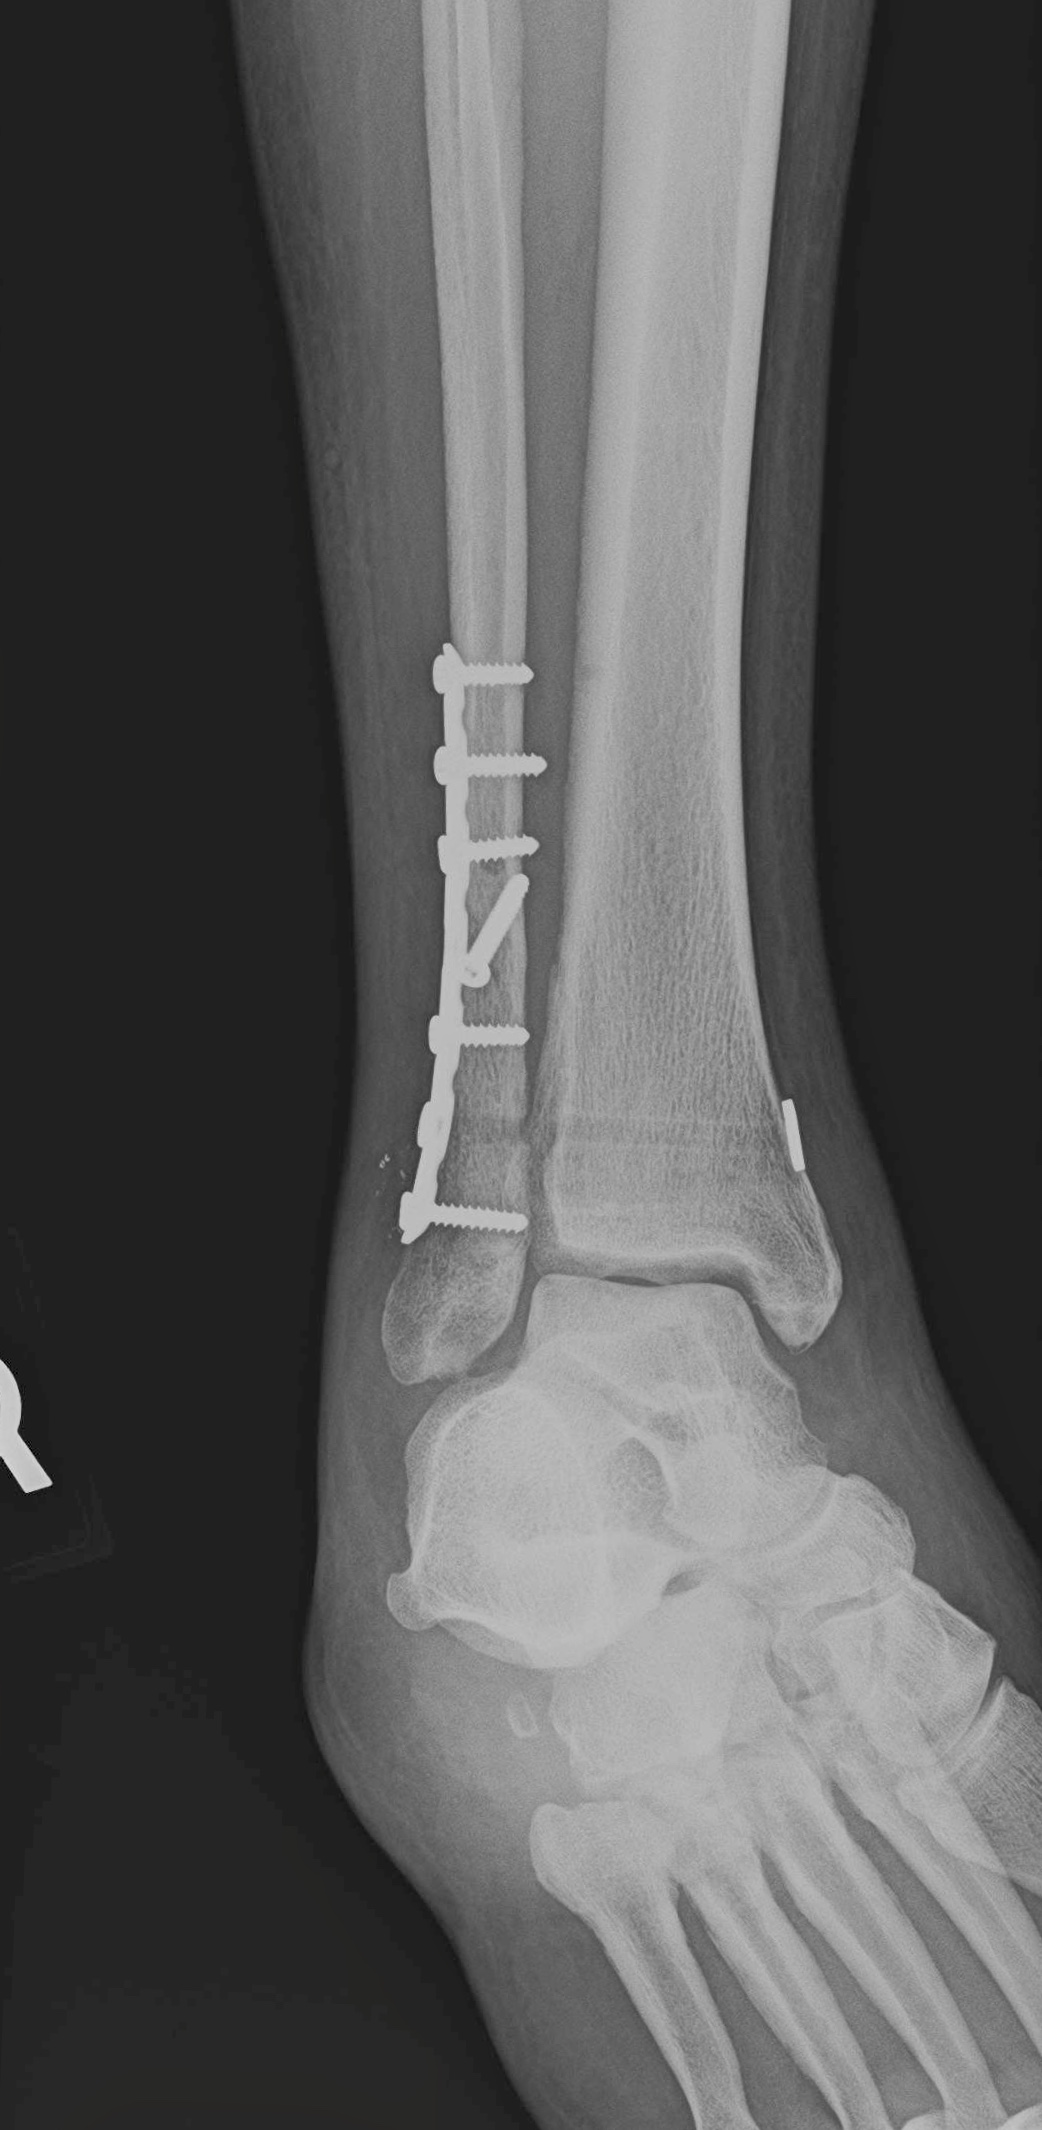

What Is An Ankle Fracture? Eugene Stautberg, MD General Orthopedic

Ankle Fracture FootEducation What Is A Buckle Fracture In The Ankle Falling on their outstretched hand is a common way that kids get buckle fractures. Several fractures, which may require surgery. They're incomplete fractures — the bone is not broken all the way. A buckle fracture is an incomplete fracture where one side of the bone buckles or bends on itself; By definition, a buckle fracture is a stable fracture and. What Is A Buckle Fracture In The Ankle.

Ankle Xray Interpretation Ankle Fracture Geeky Medics What Is A Buckle Fracture In The Ankle Michael anderson explains what this fracture is and describes how it happens. Falling on their outstretched hand is a common way that kids get buckle fractures. If the fracture is serious enough, you. A fractured ankle can range from: A simple break in one bone, which may not stop you from walking, to. This means that one or more of. What Is A Buckle Fracture In The Ankle.

Ankle Fractures Core EM What Is A Buckle Fracture In The Ankle They happen when one side of the bone buckles, or bends, but doesn’t break all the way through. Buckle fractures are a type of bone injury that happen in children. This means that one or more of the bones that make up the ankle joint are broken. A fractured ankle can range from: Buckle fractures are compression fractures and are. What Is A Buckle Fracture In The Ankle.